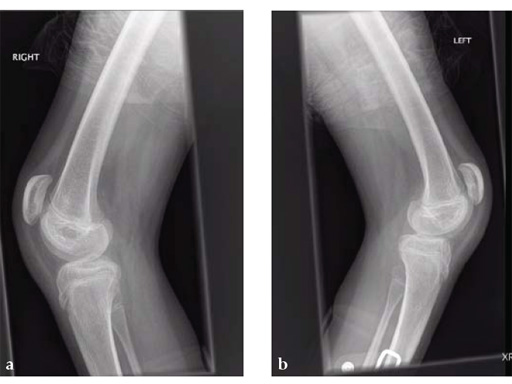

A 12-year-old girl presented for the first time to the cerebral palsy clinic. Although weak as well as spastic she was able to stand and step and wished to walk better. Physical examination revealed fixed flexion deformity of both knees. Distal femoral osteotomy with some shortening was the preferred option as hamstring lengthening and posterior knee capsule release would have caused further weakening.